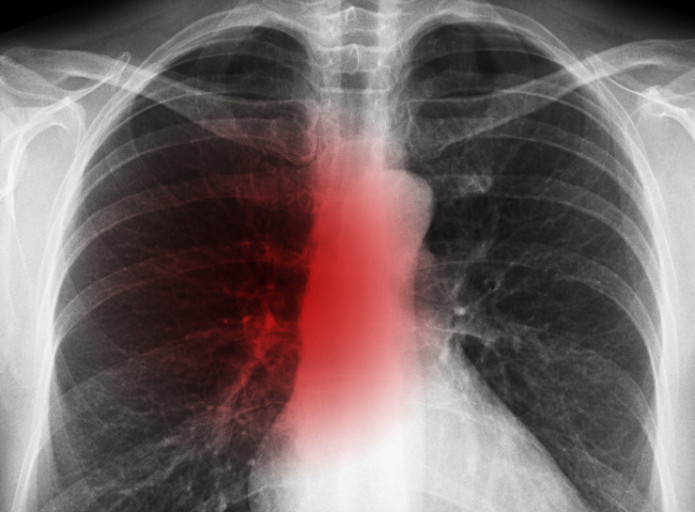

폐암은 위암, 갑상선암 다음으로 3번째로 발병 빈도가 높은 3대 암 중 한 가지인데요. 폐암은 재발과 전이까지의 빈도도 잦은지라 완치가 어렵다고 하며 폐암 발병 초기에는 거의 증상이 없을 수가 있어 수술이 불가능한 3기, 혹은 4기에 주로 진단된다고 해요.

폐암 초기증상 폐암 4기에 이르게 되면 5년 생존률이 30% 대로 감소하게 된다고 해요. 그리하여 폐암은 암 질병이자 중 사망자 비율이 가장 높은 것으로 나타나고 있어요.

폐암은 사망률 2위를 차지하고 있는 간암에 비해 무려 2배에 가까운 사망률을 보이고 있다고 합니다. 이렇게 치명적인 폐암에 대해 미리 알고 대처하는 것이 바람직할 것 같아요. 아래에서는 폐암이라 판단해 볼 수 있는 그 초기증상에 대해 간단히 설명드릴게요.